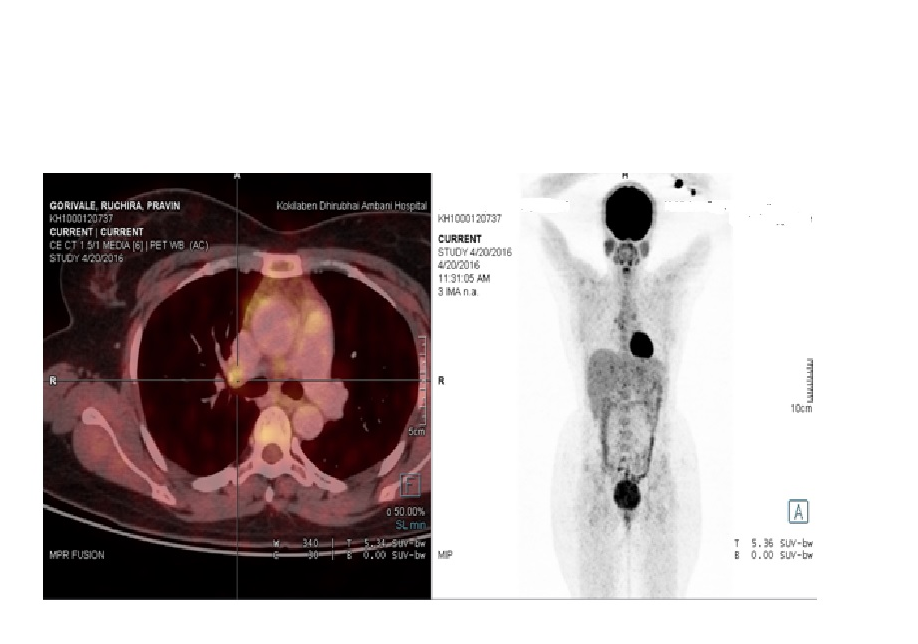

Recent literature evidence has demonstrated a small but definite increase in the risk of malignancies in SLE patients when compared to general population. The present case study reports a rare occurrence of Burkitt’s lymphoma in a 32-year-old female patient who had been diagnosed with SLE around 3 years ago. The study also discusses the possible pathophysiological links between Burkitt’s lymphoma and SLE.